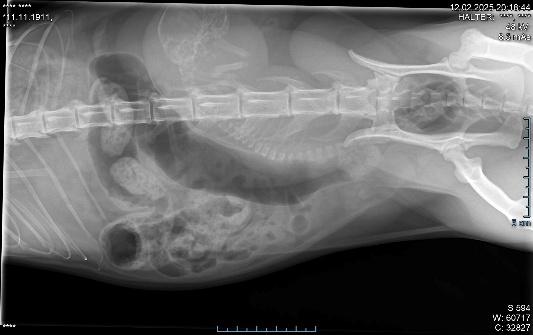

Nachtschicht-Kaiserschnitt

Ganz wichtig ist die perfekte Vorbereitung, das sterile Umfeld, schnelle und präzise Arbeit, dass das Tier nur so kurz wie möglich in Narkose bleiben muss. Und natürlich die Versorgung der Kleinen, was nicht immer einfach ist und teilweise viel Zeit in Anspruch nimmt. Der Kaiserschnitt ist nötig, wenn es max. 6 bis 12 Stunden nach Beginn der Geburt nicht weitergeht.

Bitte nicht bis zum nächsten Morgen warten, für solche Notfälle sind wir Tag und Nacht erreichbar.

Übrigens, den Beiden geht es sehr gut.